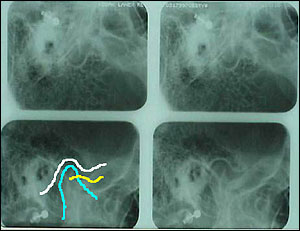

@ TMJ